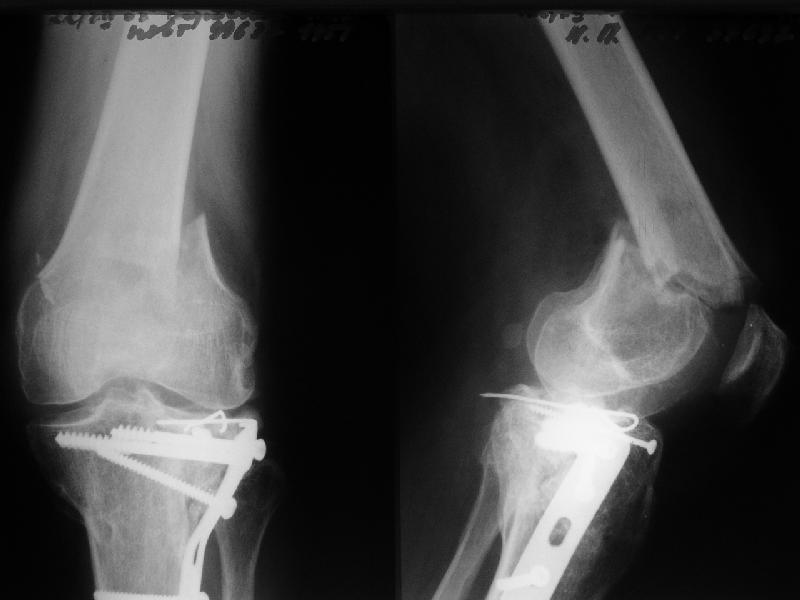

• Re: Перелом "около пластинки"

1

de> you think you are using antigrade nails for some very low

de> fractures including some intercondylar fractures.

Exactly. It seems the option looks underestimated.

No, i haven't seen such comparisons. However some advantages of closed antegrade nailing vs conventional plating looks self-evident like no site opeining, no bone skeletization, less blood loss, no need for autografting... If you or other colleagues can help me with the references it would be greatly appreciated. I would be interested also to compare ante- vs retrograde nailing for the localization.

I attached an example of C2 fracture with result of the same technique in 5 months.